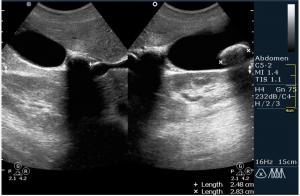

По всей видимости пузырь увеличен, напряжен, содержимое 2 крупных конкремента,один из которых вклинен.

Доктор Марио! Фиксированный камень шейки желчного пузыря. Еще один камень в просвете. Не знаю, употребляете ли Вы такой термин, но я бы еще сказал "водянка желчного пузыря". Показание к оперативному лечению желче-каменной болезни. Симптома "трехслойности стенки" не увидим. Пузырь перерастянут. Кстати, в последнее время встречается все большее и большее количество случаев желче-каменной болезни у пациентов молодого возраста. От 18 лет.

Вы совершенно правы, это холецистолитиаз с вклинённым камнем шейки (impacted GB neck stone) с перерастяжением пузыря, или водянка (GB Hydrops). Сегодня была успешнo оперирована.